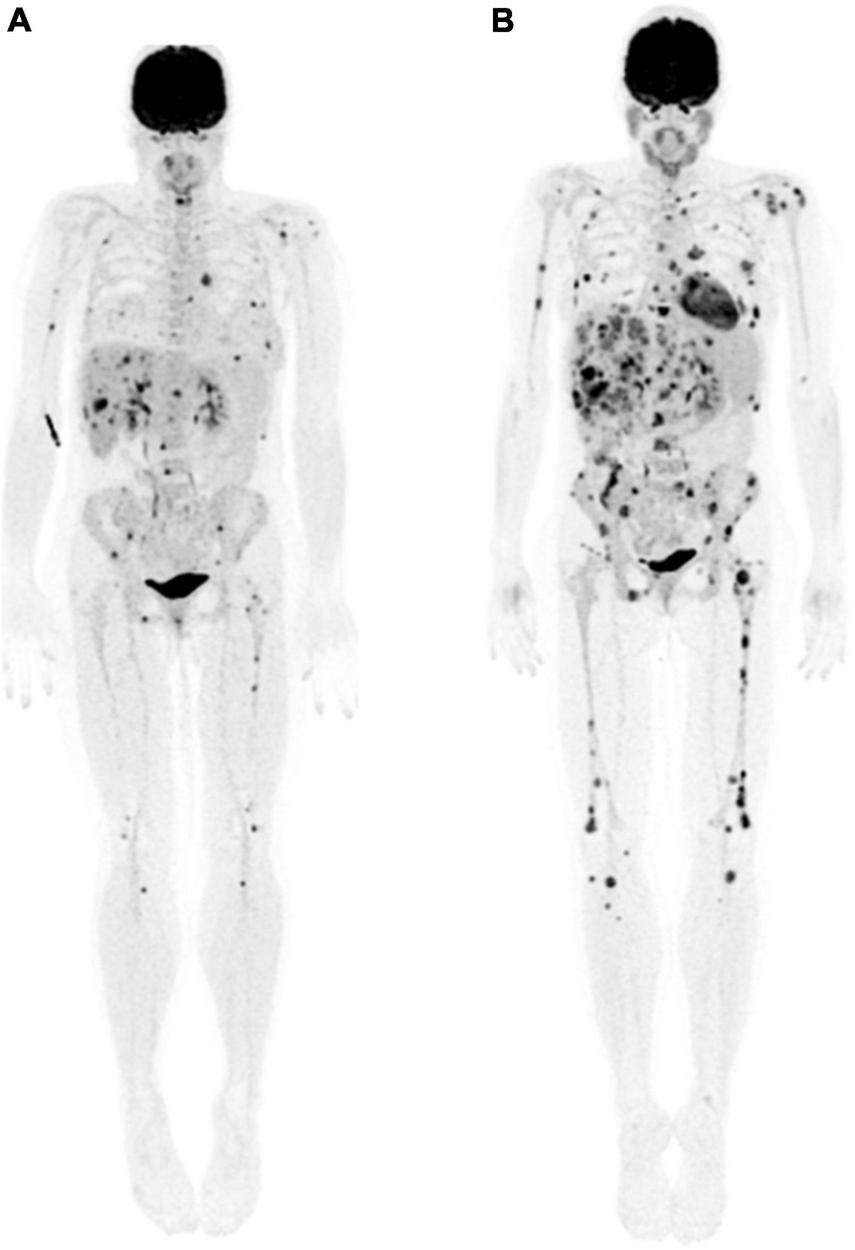

FIGURE 5

44-year-old woman with presumed stage IIIB melanoma of right buttock. (A) Maximum intensity projection whole body 18F-FDG PET image showed extensive metabolically active metastatic disease in the breasts, liver, and skeleton. (B) Three months following initiation of immunotherapy, follow-up maximum intensity projection whole body 18F-FDG PET image showed interval development of innumerable new liver, skeletal and breast lesions, most with diameter <15 mm, in keeping with progressive disease according to PERCIMT criteria.